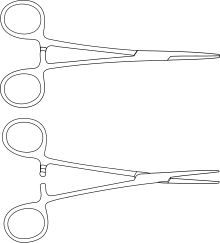

| Kelly forceps |  |

hemostatic forceps | |

| Mosquito forceps |  |

hemostatic forceps | |